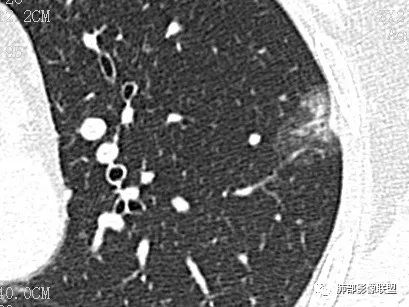

case2 医学百科网 | YxBaike.Com

男 48 2019-05-04 医学百科网 | YxBaike.Com

2019-11-11 医学百科网 | YxBaike.Com

Clover:

鳞癌 医学百科网 | YxBaike.Com

泥沙样钙化,坏死明显,支气管阻塞,阻塞肺炎

分叶,血管凹陷进入,内坏死,壁厚薄不均,坏死边界不清,肺门淋巴结大,鳞癌

右肺下叶肿块,湖泊样坏死,壁厚薄不均匀,肺门淋巴节肿大,考虑鳞癌 医学百科网 | YxBaike.Com

厚璧空洞伴不均一致坏死,支气管堵塞伴阻塞性肺炎,考虑鳞癌

分叶,无毛刺,坏死明显,壁厚薄不均,阻塞性肺炎,复查壁变得更薄,支持鳞癌

厚壁空洞分叶状,近端支气管壁增厚,湖泊样坏死,治疗23天后坏死增多,周围炎症有吸收,增强其内血管显示欠清,考虑鳞癌

病理诊断

鳞癌

一句话小结:

右肺下叶背段不规则块影,浅分叶,密度不均,轻度强化,壁厚不均,坏死及空洞明显。病灶边界可分辨,相关支气管狭窄截断。肺门见肿大淋巴结。 医学百科网 | YxBaike.Com

符合典型肺鳞癌影像学表现。 医学百科网 | YxBaike.Com

半年后任由块影坐大匪夷所思。